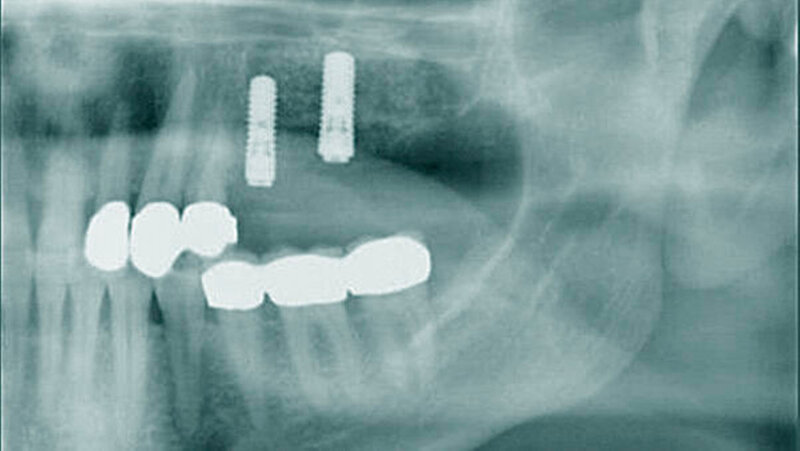

Es ist bekannt, dass Patienten mit Diabetes mellitus häufiger und schwerer von Parodontitis betroffen sind [Bascones-Martinez et al. 2014]. Lange Zeit galt die Erkrankung als eine relative Kontraindikation für die dentale Implantologie, da auch hier von Störungen der Wundheilung und knöchernen Integration ausgegangen wurde. Auch eine erhöhte Rate an Periimplantitis und Implantatversagen wurde postuliert.

• Die dentale Rehabilitation mit Zahn- implantaten bei Patienten mit Diabetes mellitus stellt ein sicheres und vorhersag- bares Verfahren dar.

• Patienten mit schlecht eingestelltem Diabetes mellitus scheinen eine verzögerte Osseointegration nach der Implantation aufzuweisen. Nach einem Jahr scheint es jedoch keinen Unterschied in der Implantatstabilität zwischen Diabetikern und gesunden Personen zu geben, auch nicht bei schlecht eingestelltem HbA1c.

• Diabetes mellitus scheint in den ersten Jahren kein erhöhtes Risiko für periimplantäre Entzündungen darzustellen. Im Gegensatz dazu scheint das Risiko für periimplantäre Entzündung mit steigender Dauer nach der Implantation anzusteigen.

• Die Überlebensraten von Implantaten zeigen bei Diabetikern in Studien von bis zu sechs Jahren keine signifikanten Unterschiede zu Nicht-Diabetikern, in einem Beobachtungszeitraum bis zu 20 Jahren ist eine reduzierte Implantat-Überlebensrate bei Diabetikern erkennbar.

• In der Literatur finden sich keine Hinweise darauf, dass Augmentationsverfahren wie guided bone regeneration und Sinuslift eine höhere Komplikations- und Fehlerrate bei Patienten mit gut eingestelltem Diabetes mellitus aufweisen.